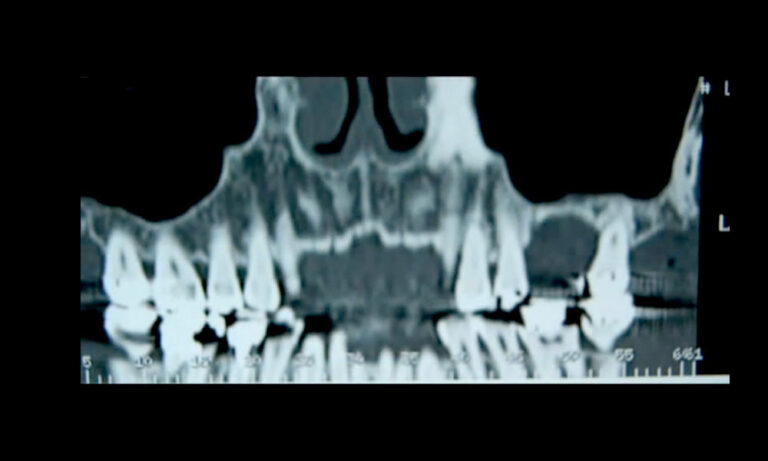

Lower Impacted (Orthodontics)